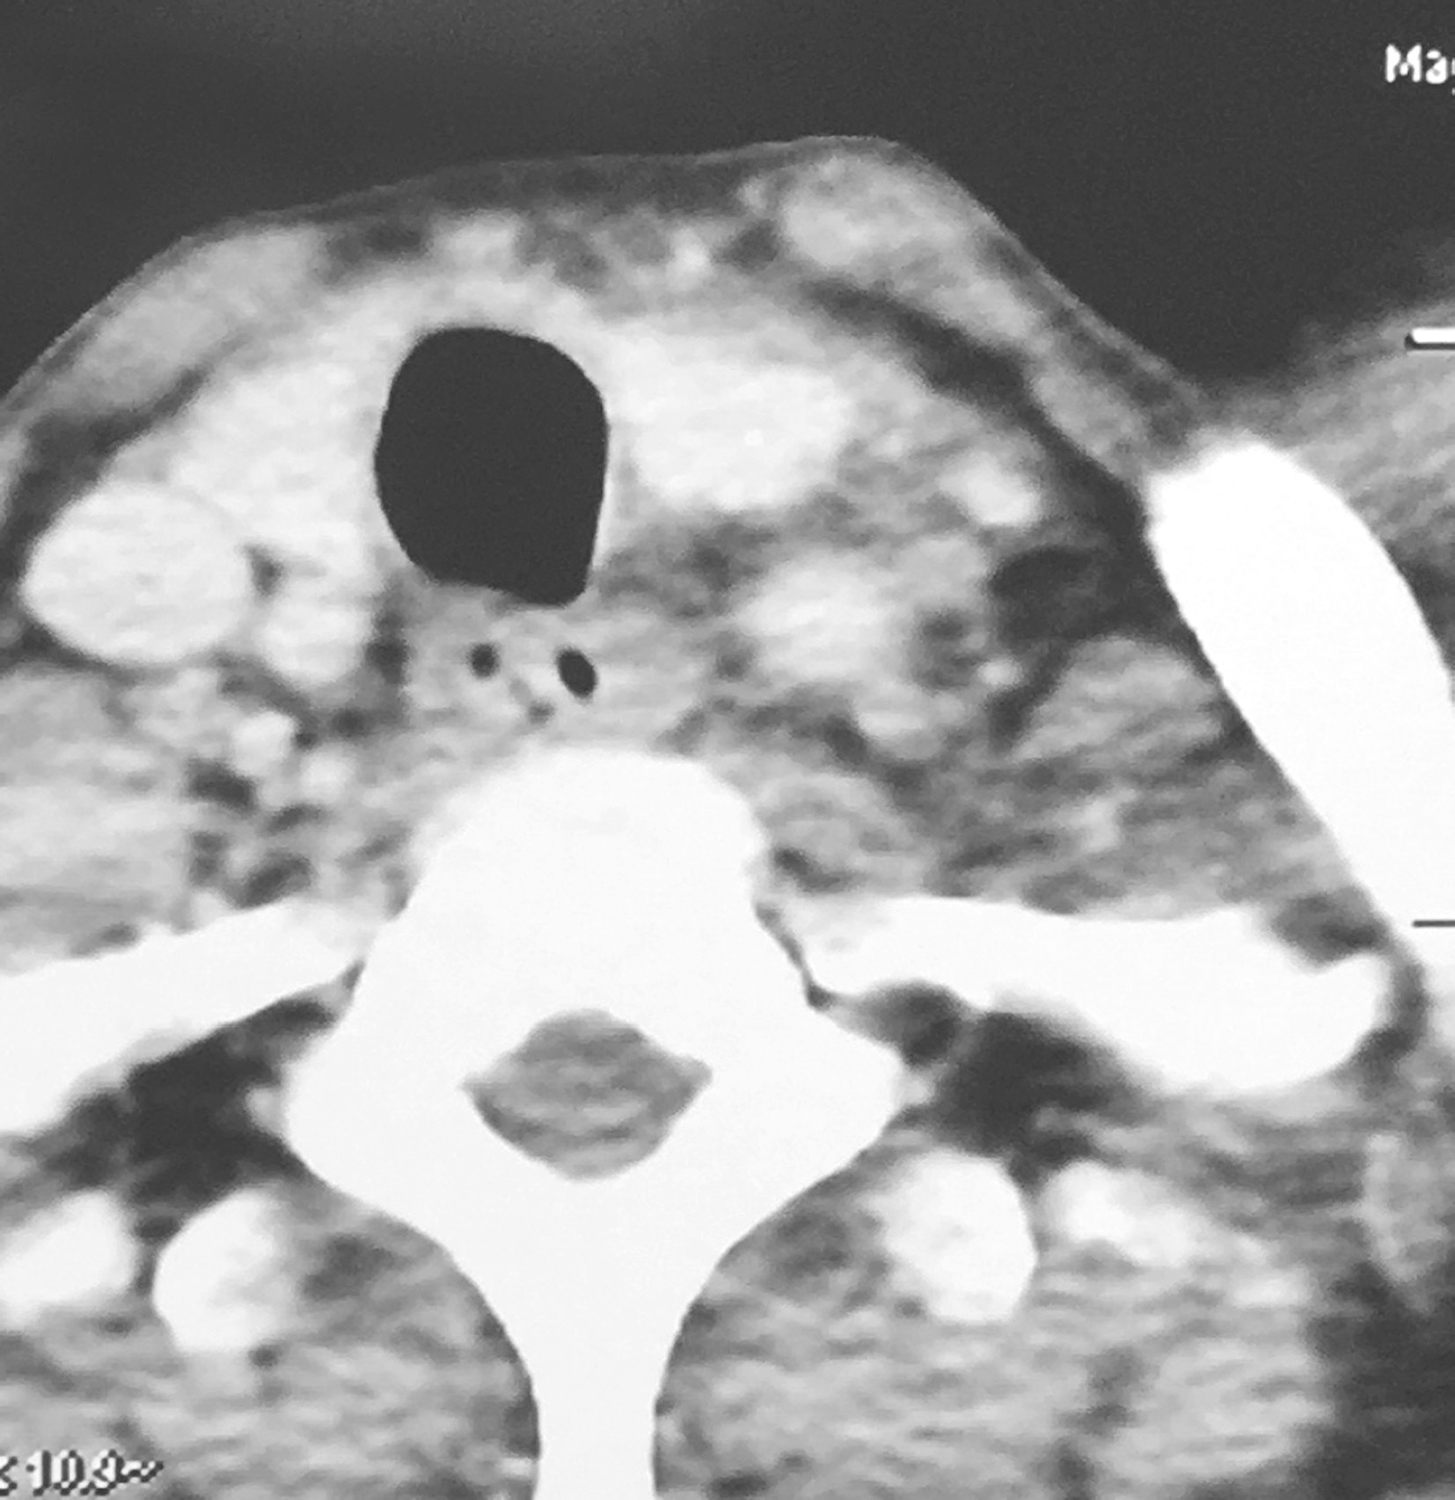

3.颈胸强化CT检查

①下咽部左梨状窝区可见软组织密度影,增强扫描可强化,向内累及左侧半喉,侵犯会厌前间隙、声门旁间隙,肿瘤侵透甲状软骨板、舌骨、累及咽侧壁及下咽后壁(图1、图2),向下累及环后区及颈段食管,向外侵犯喉外肌肉及颈前软组织。颈动脉鞘周围多枚肿大淋巴结,部分融合,边界不清,与咽喉肿瘤及颈前肌肉融合,右侧甲状腺受侵(图3),颈内静脉闭塞(图4),颈总动脉与肿瘤边界不清。右侧颈鞘周围也可见多枚肿大淋巴结,增强扫描可见强化。②双肺纹理增粗,双肺野及纵隔内未见异常。

影像学诊断:符合下咽部恶性肿瘤累及喉,双颈部多发淋巴结转移表现。

图1下咽部左梨状窝区可见软组织密度影,增强扫描可强化

图2向内累及左侧半喉,侵犯会厌前间隙、声门旁间隙,肿瘤侵透甲状软骨板、舌骨、累及咽侧壁及下咽后壁